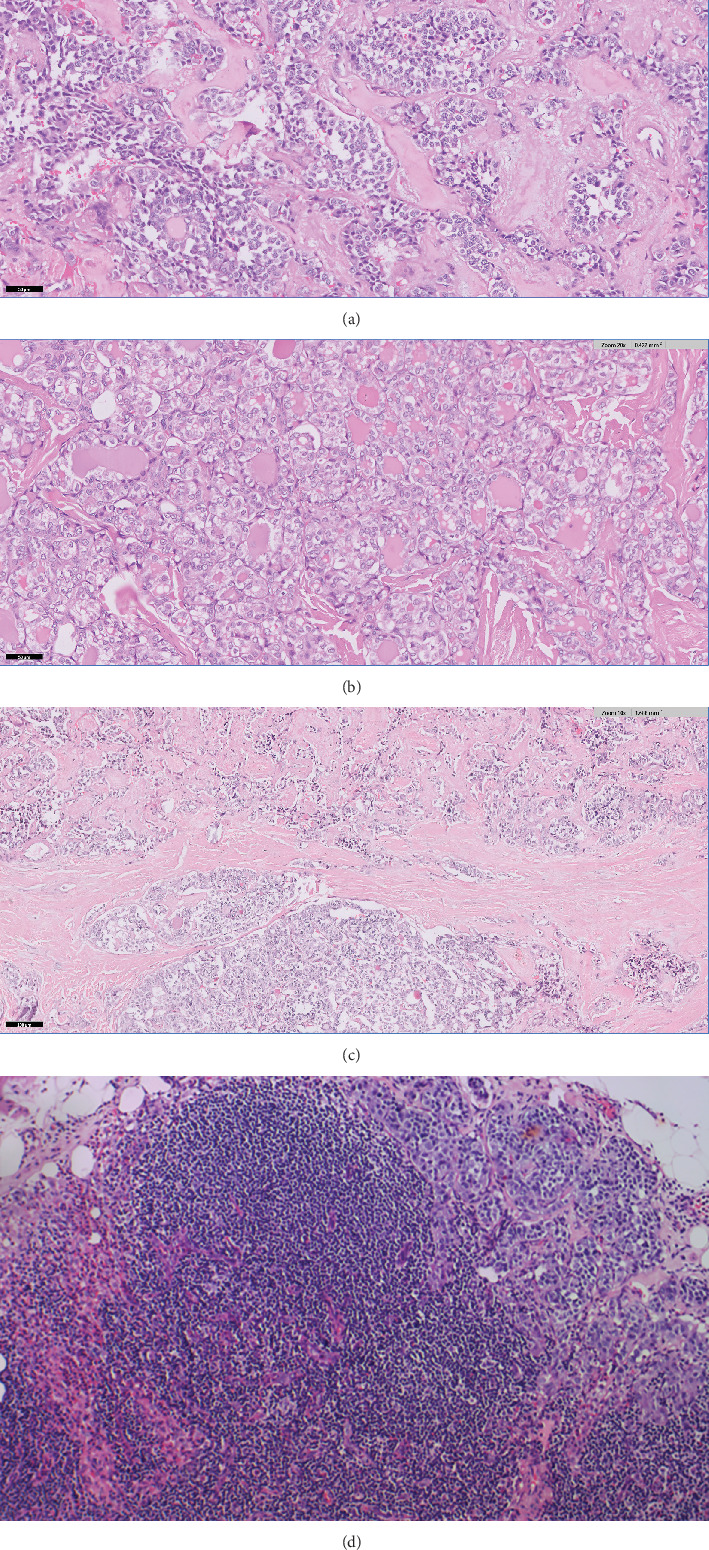

碰撞瘤是一种罕见的肿瘤,由两个形态不同的肿瘤在同一器官内组成,没有组织学上的混杂。甲状腺碰撞瘤极为罕见。我们报告一例64岁男性患者放射学上可疑的甲状腺右叶TI-RADS-TR4病变。细针穿刺细胞学检查诊断为甲状腺髓样癌。行甲状腺全切除术并中央及右侧颈外侧清扫术。经组织病理学检查,发现碰撞瘤。碰撞肿瘤的组成为多灶性甲状腺髓样癌(MTC)和多灶性浸润性滤泡变异型甲状腺乳头状癌(PTC)。关于碰撞瘤的发病机制,人们提出了几种假说。肿瘤的进一步处理和预后取决于具有较高分期和更具侵袭性行为的成分。病例报告强调需要对标本中未涉及的区域进行彻底采样,以便对每个组成部分进行显微镜评估和分期。

Collision tumors are rare tumors comprising two morphologically distinct tumors within the same organ without histological admixture. Thyroid collision tumors are extremely rare. We present a case of a 64-year-old male patient with a radiologically suspicious, TI-RADS-TR4 lesion in the right lobe of the thyroid. Fine needle aspiration cytology (FNAC) from the lesion was diagnosed as medullary thyroid carcinoma. Total thyroidectomy with central and right lateral neck dissection was performed. On histopathological evaluation, a collision tumor was identified. Components of the collision tumor were multifocal medullary thyroid carcinoma (MTC) and multifocal infiltrative follicular variant of papillary thyroid carcinoma (PTC). Several hypotheses have been suggested regarding the pathogenesis of the collision tumor. Further management and prognosis of the tumor depend on the component with the higher stage and more aggressive behavior. The case report emphasizes the need for thorough sampling of uninvolved areas in the specimen for microscopic evaluation and staging of each component.